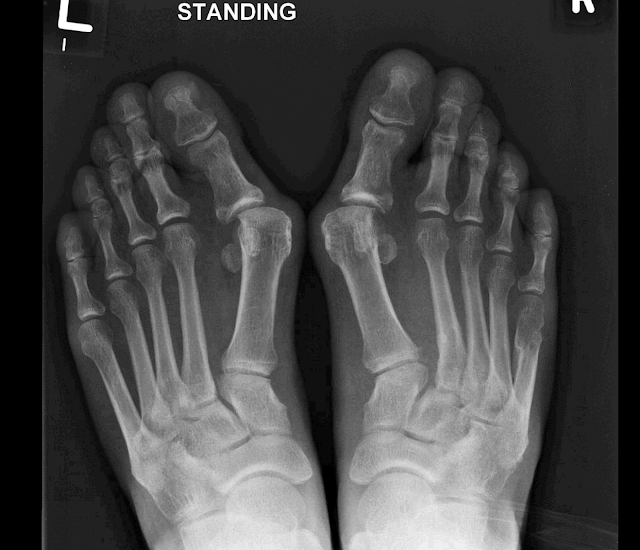

As you can see all had x-ray findings consistent with a lisfranc injury. They were allowed to be weight bearing as tolerated in a cast boot and transitioned to a hard sole shoe / hiking boot as pain and swelling decreased. The average time was between 6 to 12 weeks.

Case 12 - patient had evident lisfranc injury on right side. Patient was transitioned from a cast boot to a hard soled shoe. At 9 weeks patient no longer had pain and was able to perform a single heel raise. As such we opted not to proceed with a lisfranc fusion procedure.